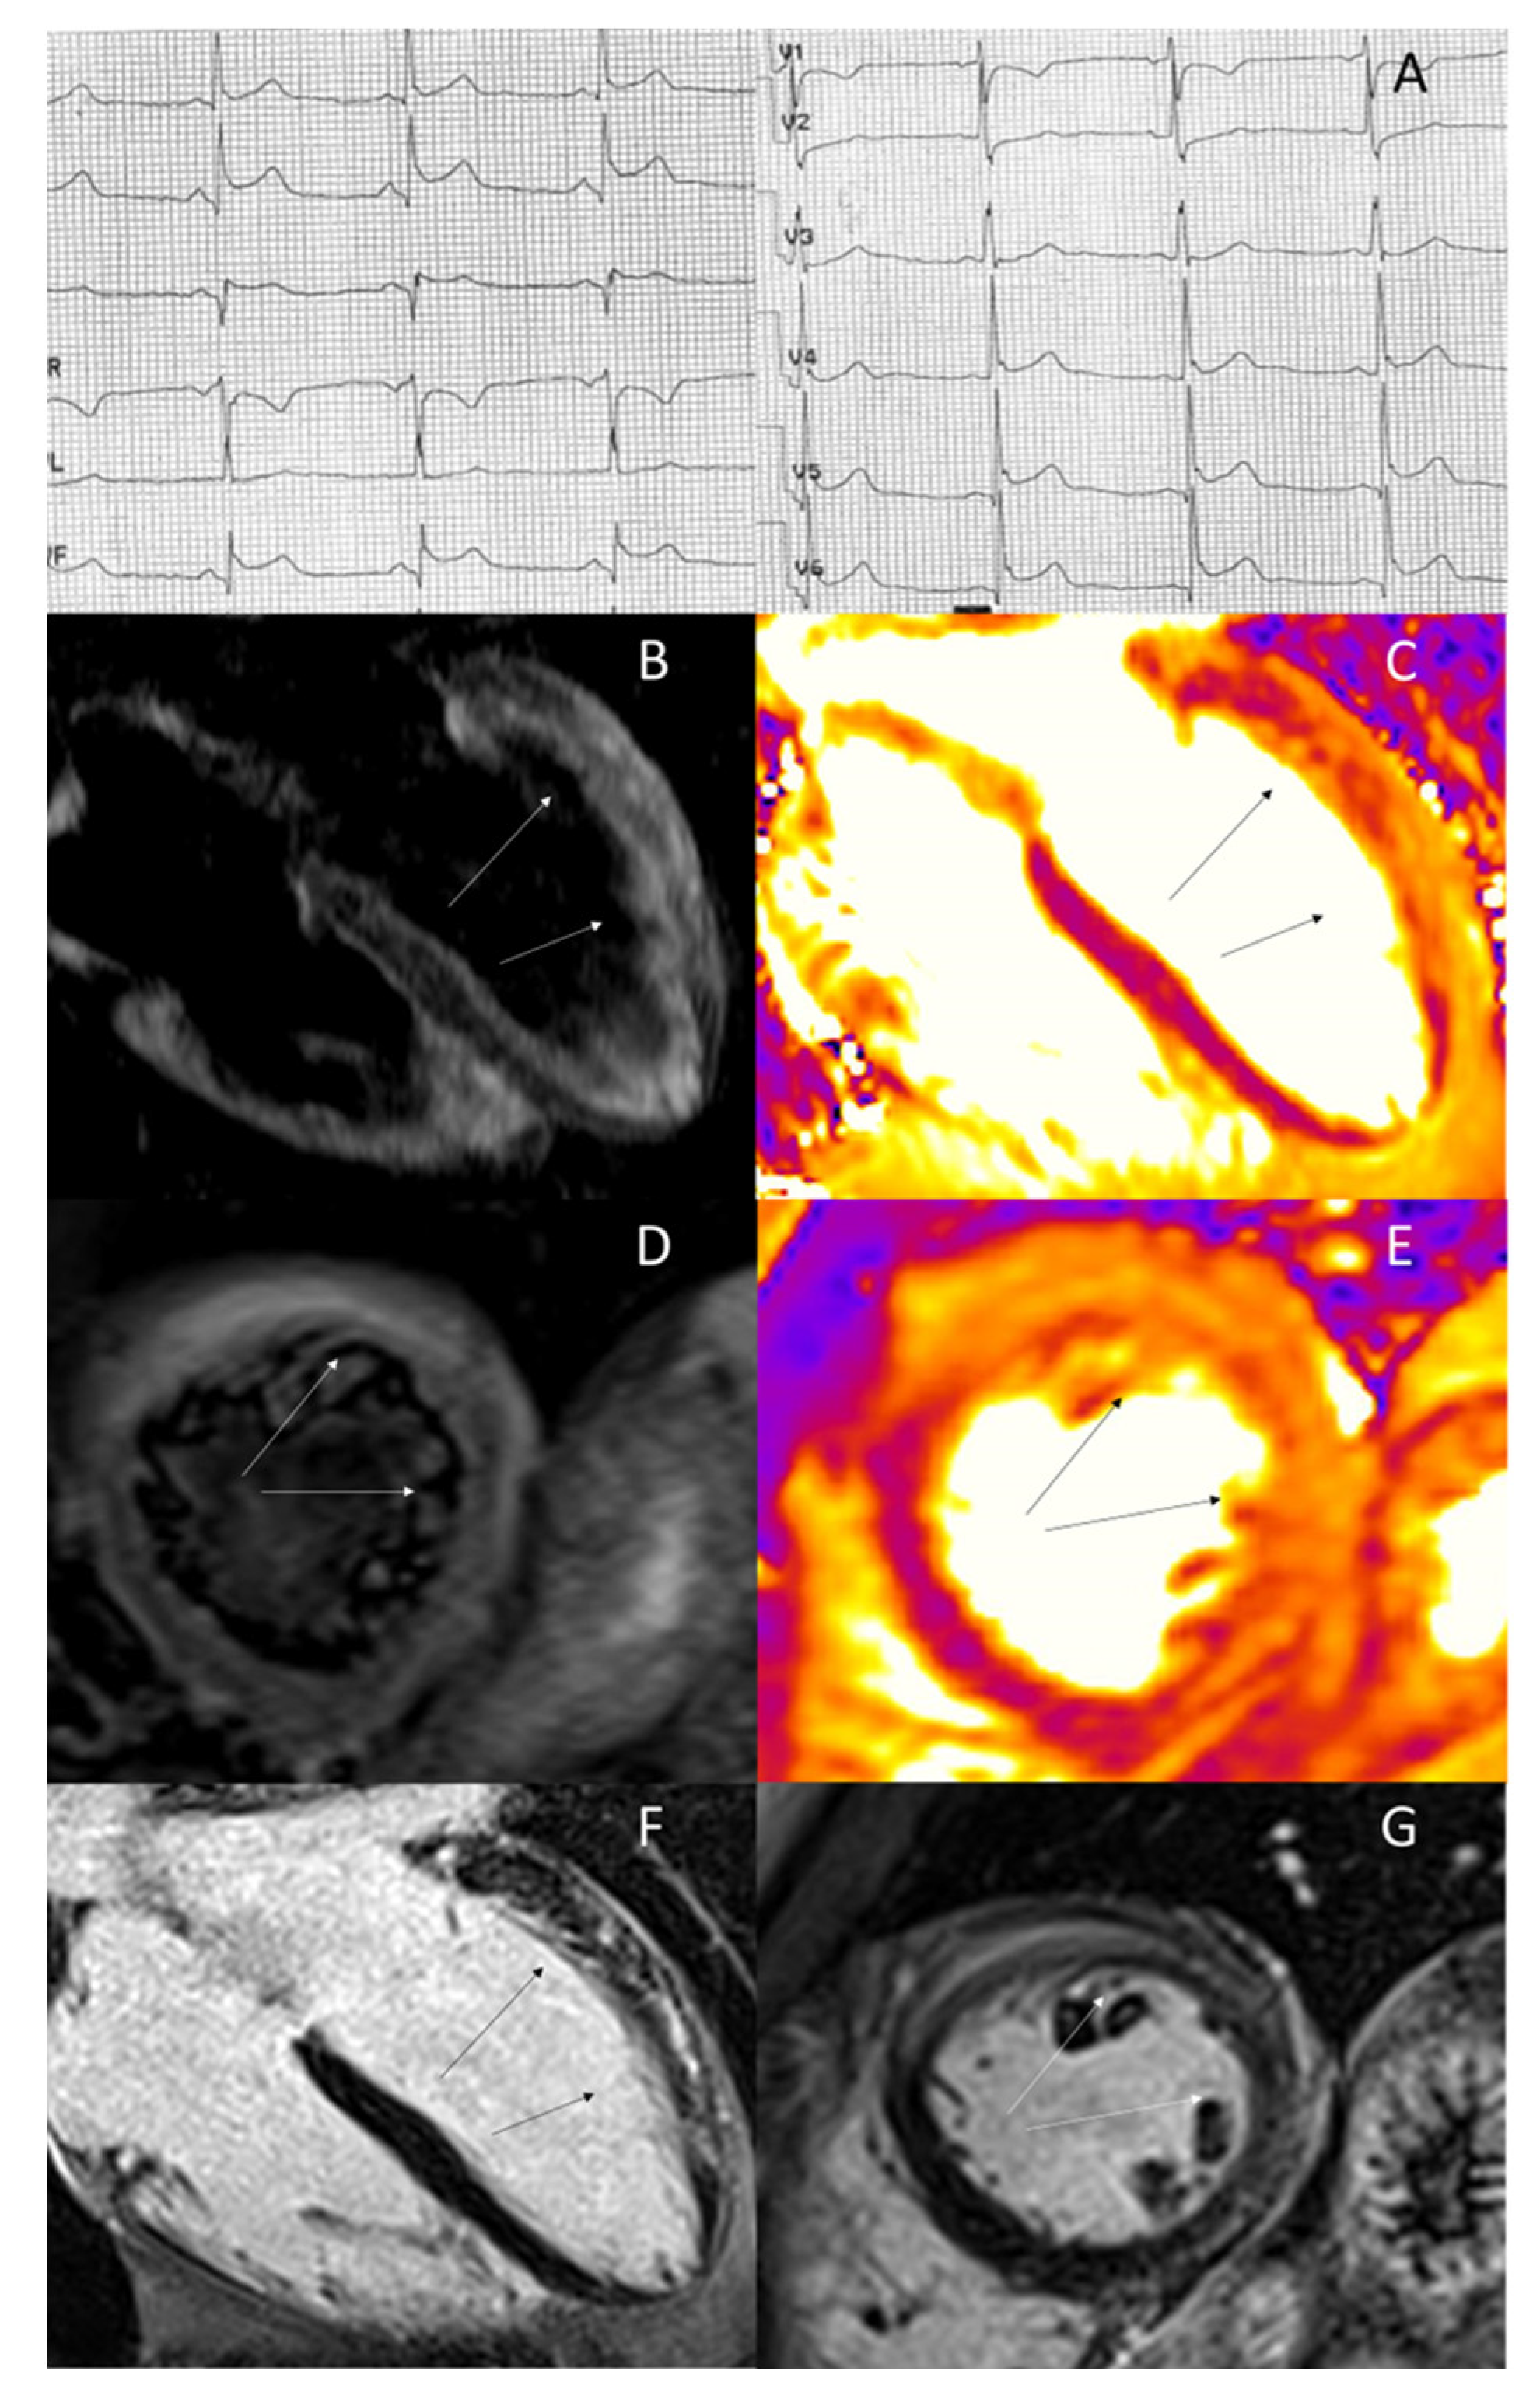

- Perazzolo Marra, M.; Zorzi, A.; Corbetti, F.; De Lazzari, M.; Migliore, F.; Tona, F.; Tarantini, G.; Iliceto, S.; Corrado, D. Apicobasal gradient of left ventricular myocardial edema underlies transient T-wave inversion and QT interval prolongation (Wellens’ ECG pattern) in Tako-Tsubo cardiomyopathy. Heart Rhythm 2013, 10, 70–77. [Google Scholar] [CrossRef]

- Migliore, F.; Zorzi, A.; Marra, M.P.; Basso, C.; Corbetti, F.; De Lazzari, M.; Tarantini, G.; Buja, P.; Lacognata, C.; Thiene, G.; et al. Myocardial edema underlies dynamic T-wave inversion (Wellens’ ECG pattern) in patients with reversible left ventricular dysfunction. Heart Rhythm 2011, 8, 1629–1634. [Google Scholar] [CrossRef]

- Zorzi, A.; Perazzolo Marra, M.; Migliore, F.; De Lazzari, M.; Tarantini, G.; Iliceto, S.; Corrado, D. Relationship between repolarization abnormalities and myocardial edema in atypical Tako-Tsubo syndrome. J. Electrocardiol. 2013, 46, 348–351. [Google Scholar] [CrossRef]

- Migliore, F.; Zorzi, A.; Perazzolo Marra, M.; Iliceto, S.; Corrado, D. Myocardial edema as a substrate of electrocardiographic abnormalities and life-threatening arrhythmias in reversible ventricular dysfunction of takotsubo cardiomyopathy: Imaging evidence, presumed mechanisms, and implications for therapy. Heart Rhythm 2015, 12, 1867–1877. [Google Scholar] [CrossRef] [PubMed]